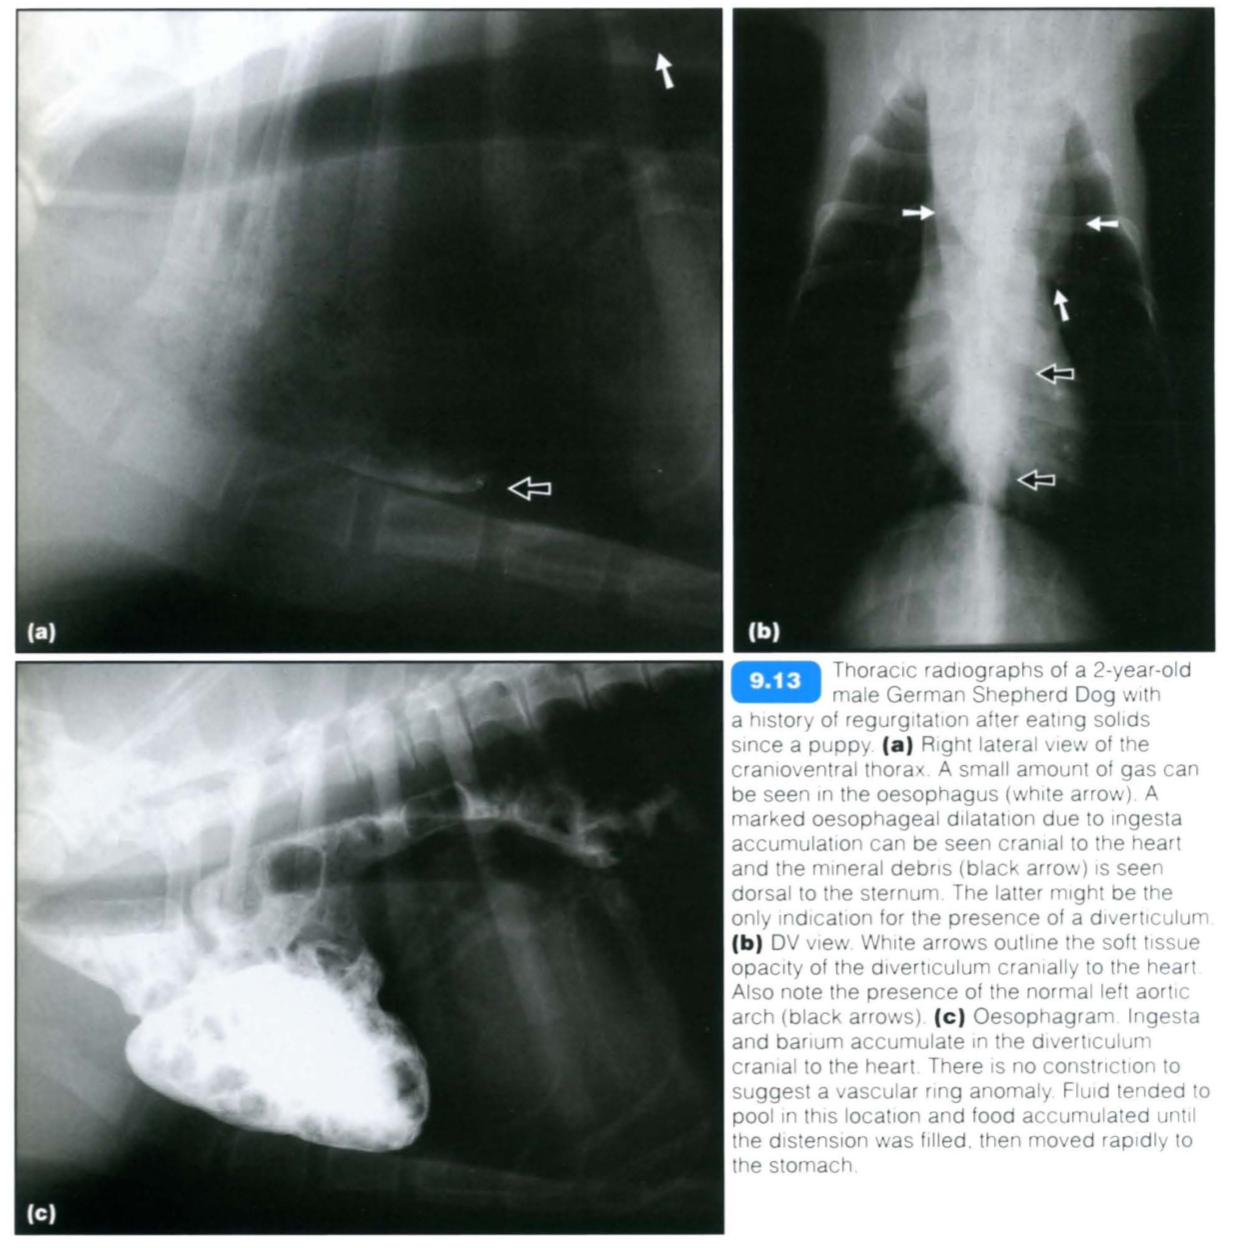

Oesophageal diverticula are rare pouch-like sacculations of the oesophageal wall that may be congenital (Figure 9.13) or acquired. Congenital diverticula occur most often in medium-sized to small-breed dogs. Clinical signs of diverticula are related to the underlying oesophageal disease or to local food stasis and inflammation.

The accumulation of ingesta within the diverticulum leads to oesophagitis, mechanical obstruction (seen with large diverticula) and disturbed oesophageal motility. Severe cases with mucosal ulceration may eventually perforate, resulting in mediastinitis.

Diverticula should not be confused with a normal redundant oesophagus. Extending the patient’s neck should result in the disappearance of a ‘false diverticulum.